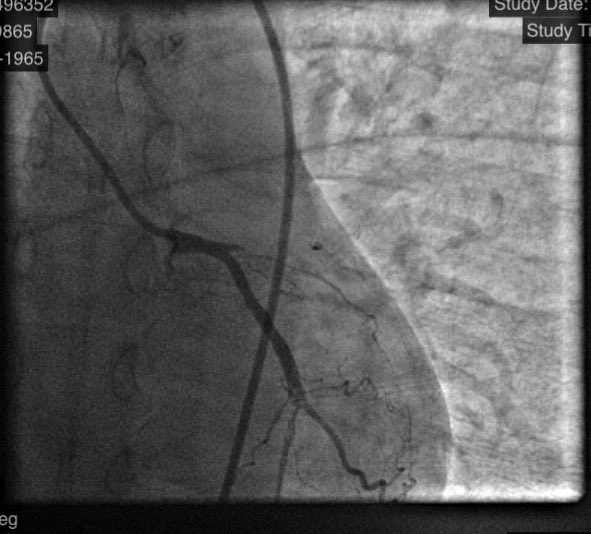

45f #cardiotwitter #safefemoral ,2 hrs symptoms,3am case, #stemi stent into left main from LAD.no#shock ,no#impella. EF40.#alifesaved

istentem's tweet image. 45f #cardiotwitter #safefemoral ,2 hrs symptoms,3am case, #stemi stent into left main from LAD.no#shock ,no#impella. EF40.#alifesaved